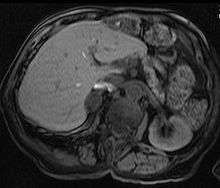

Adrenal

Adrenal adenomas are common, and are often found on the abdomen, usually not as the focus of investigation; they are usually incidental findings. About one in 10,000 is malignant. Thus, a biopsy is rarely called for, especially if the lesion is homogeneous and smaller than 3 centimeters. Follow-up images in three to six months can confirm the stability of the growth.

While some adrenal adenomas do not secrete hormones at all, often some secrete cortisol, causing Cushing's syndrome, aldosterone causing Conn's syndrome, or androgens causing hyperandrogenism.